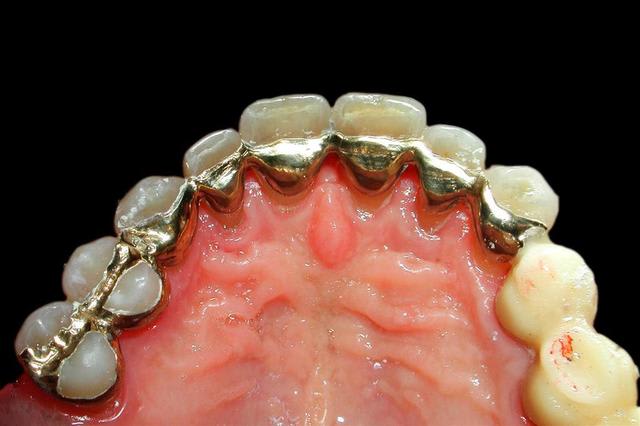

Pourtant j'en ai fait des contentions...(Attelle or avec pins, cavalier, Ribbond, etc etc...)

Quelques photos jointes pour vous'assurer que je ne bluffe pas ;)